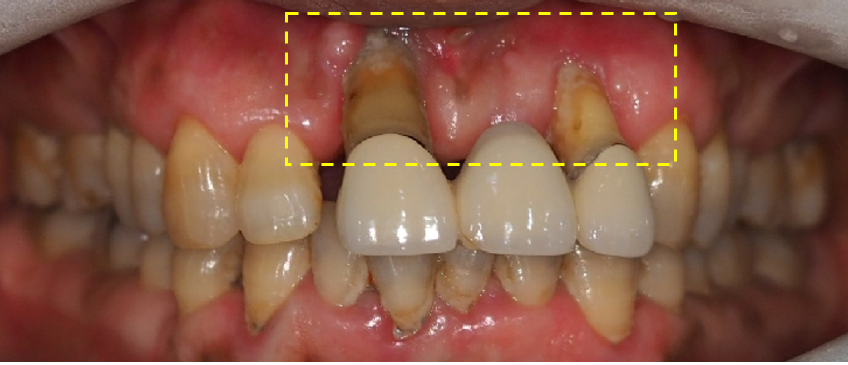

오늘은 소개 해드릴 환자분은 심한 치은 퇴축을 갖고 계시다가 치아가 많이 흔들려서 내원 해주셨는데요

먼저 구강 사진 부터 보도록 할께요.

표시 된곳을 보시면 심한 치은이 심하게 퇴축되어 잇몸의 뿌리까지 노출된 상태 입니다.

치은 퇴축은 잇몸이 치아 뿌리 방향으로 하향되어 치근이 드러나는 현상 인데요.

치아 뿐만 아니라 주변뼈와 조직에도 영향 주게 됩니다.